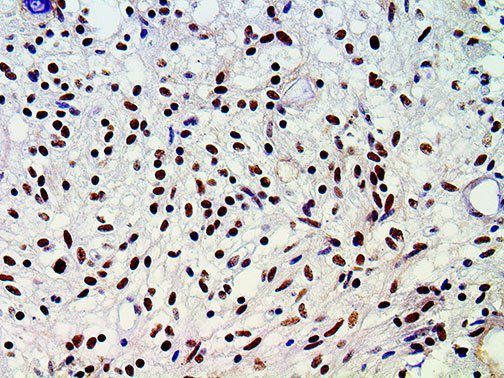

It is the ICU physician who is most likely to witness one of the deadliest manifestations of the abnormal immunological response, the cytokine storm syndrome (CSS). This response is also referred to by some as the cytokine release syndrome (CRS). CSS is characterized by continuous activation and expansion of macrophage and lymphocyte populations, which secrete large amounts of cytokines, causing the cytokine storm. This massive cytokine release is akin to hemophagocytic lymphohistiocytosis (HLH) disease, a syndrome characterized by initial unchecked and persistent activation of cytotoxic T lymphocytes and NK cells.

Clinical and laboratory manifestations of HLH include fever, enlarged liver and/or spleen, neurologic dysfunction, coagulopathy, liver dysfunction, cytopenias (i.e., low levels of erythrocytes, leukocytes, and/or platelets), hypertriglyceridemia, hyperferritinemia, hemophagocytosis, and eventually diminished NK cell activity as the immune system becomes progressively paralyzed. HLH can be familial (primary HLH) or secondary to another disease process (sHLH), such as rheumatic disease, in which it is referred to as macrophage activation syndrome (MAS, characterized by elevated ferritin).